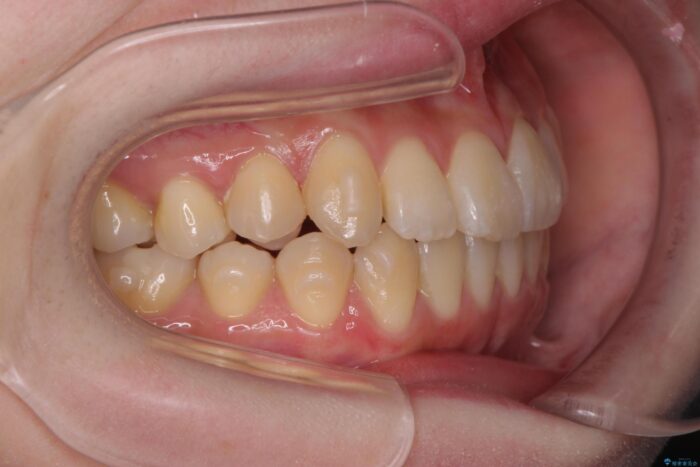

前歯のねじれが気になる、歯並びを改善したいとご来院された患者様です。

歯のねじれをきれいに取るのは、インビザライン(マウスピース矯正)だけでは難しい動きです。そのため、事前に4か月間の部分ワイヤー矯正を行い、治療期間を短くし、より美しい仕上がりを目指す計画です。